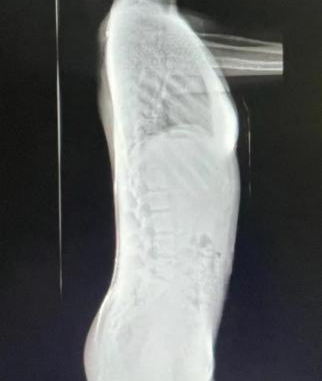

脊柱侧凸检查影像